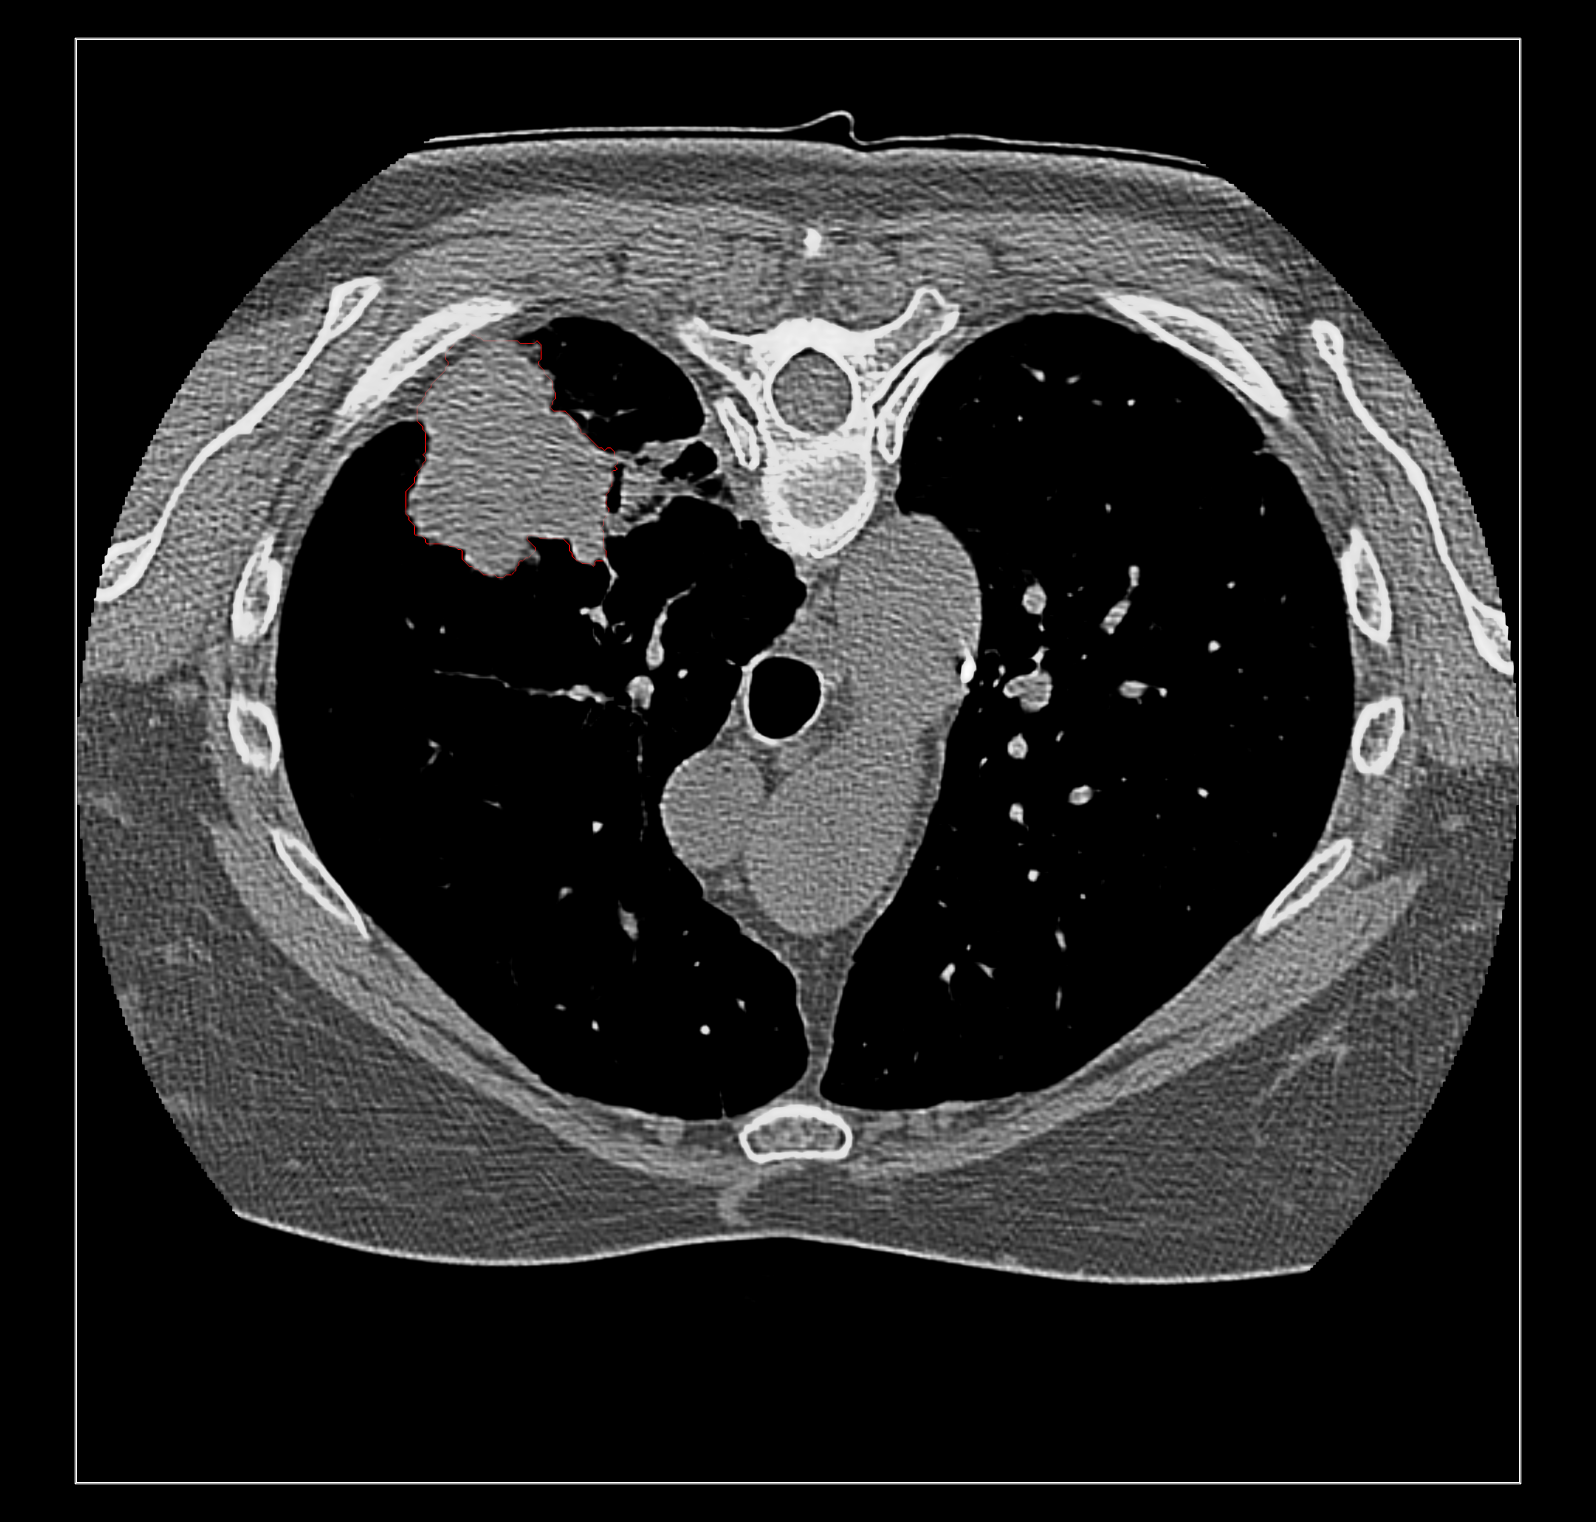

Surface rendering of segmentation channels avoids this problem. But I suspect coloring the image data according to the segmentation is far more useful to researchers looking at medical imaging because unlike a surface it allows you to see the intensities in the segmented region. For instance that helps you judge if the segmentation is correct. Sometimes a surface is best, for instance if you just want to see the size of a segmented tumor or compare the size a month ago to now using transparent surfaces can do that. I guess my overall assessment is that good quality medical imaging visualization needs the fancier blending. Because medical imaging is significantly different from electron and light microscopy there will be different needs that may be hard to implement like this blending problem. The priority of such time consuming improvements needs to be guided by medical imaging users.

Surface rendering of a segmentation with image rendering of a CT scan can look ok, and only the outline of the surface can be shown using volume command "capFaces false". Showing both segmentation and CT as image also works fine if the brightness curve is not narrow. I've attached images for all 3 styles made with